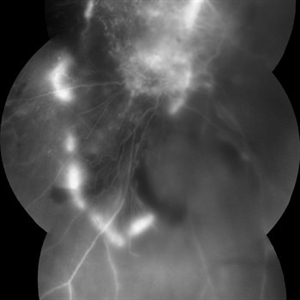

FA 5 min - Large Hemorrhage With Macular Detachment Due to AMD

Nov 7 2019 by John S. King, MD

81-year-old white female with three day history of seeing a "dark blob" nasally OD; no blood thinners; vision was 20/100- J16 with 2+NSC OD; OCT (not shown) had large SRF that included the fovea and extended out temporally. Posterior segment showed a large amount of SRF in the macula with some SRH in the inferior portion of the macula, hemorrhagic PEDs temporally with some RPE scarring and SRH in the periphery. On the FA there is blockage by the SRH and SRPE heme; there is staining peripherally; there is a wavbe of leakage that extends out into the macula and pools into to subretinal space.

Photographer: Brandon Peter

Condition/keywords: retinal pigment epithelium, subretinal hemorrhage, wet age-related macular degeneration (wet AMD)